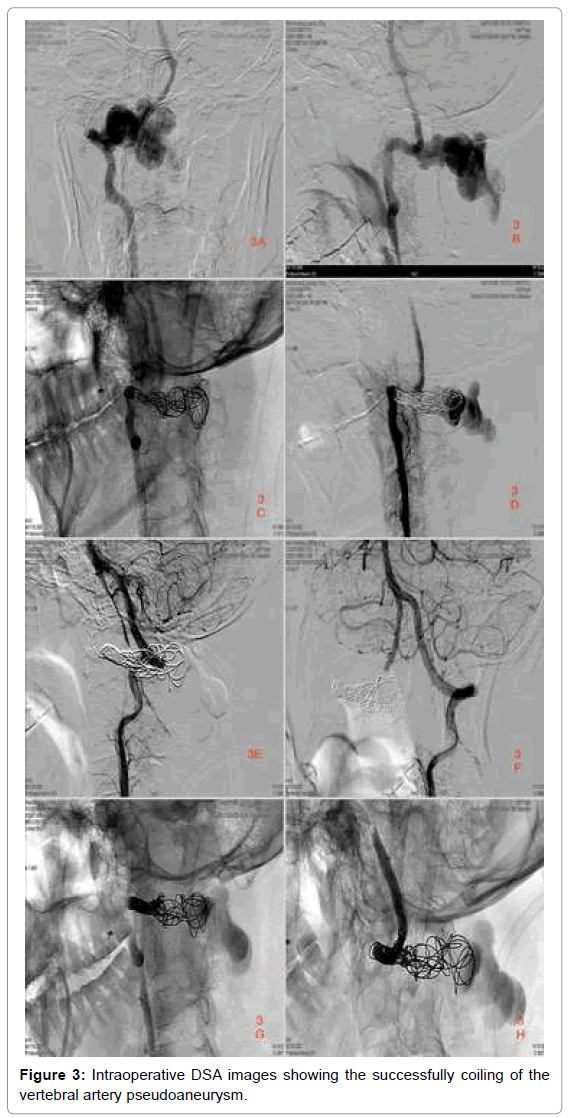

vascularmedicinesurgeryvertebralarterypseudoaneurysm Coil Embolization Of Vertebral Artery For anatomical reasons, the surgical management of vai is difficult, and endovascular management often yields a good outcome. Coiling of small superior cerebellar artery aneurysms (sscaas) is challenging. We aimed to describe anatomic considerations in. Two microcatheters, inserted proximal and distal to the injury sites, were. Coil Embolization Of Vertebral Artery.